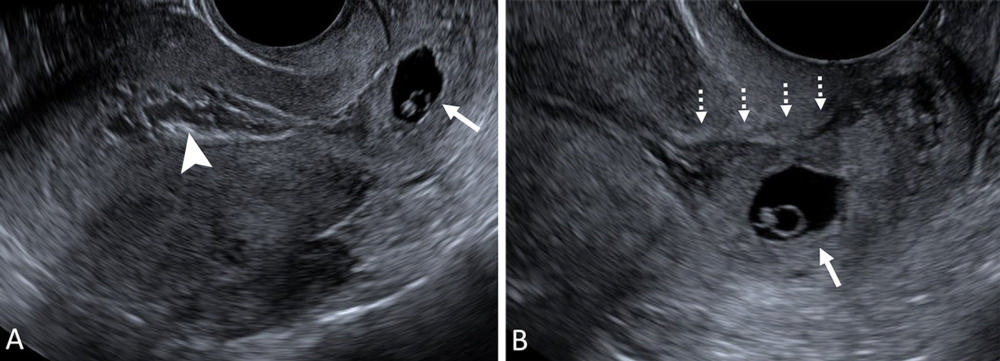

Figure 6. Normal intrauterine pregnancy (IUP) variant: eccentrically located gestational sac (GS) completely surrounded by endometrium. (A) Transvaginal transverse grayscale and (B) coronal reformatted three-dimensional US image in a 36-year-old pregnant patient shows an off-midline (leftward) GS (arrow) at 5 weeks 4 days with yolk sac and embryo. The GS is completely surrounded by endometrium and may be reported as an IUP without further description. If desired, the user may describe as an eccentrically located GS completely surrounded by endometrium but should conclude as an IUP to obviate concern for an interstitial ectopic pregnancy. The terms ‘angular’ or ‘cornual pregnancy’ should be avoided. Coronal reformatted three-dimensional US may help confirm a GS is located within endometrium, as demonstrated in this case.

High-res (TIF) version